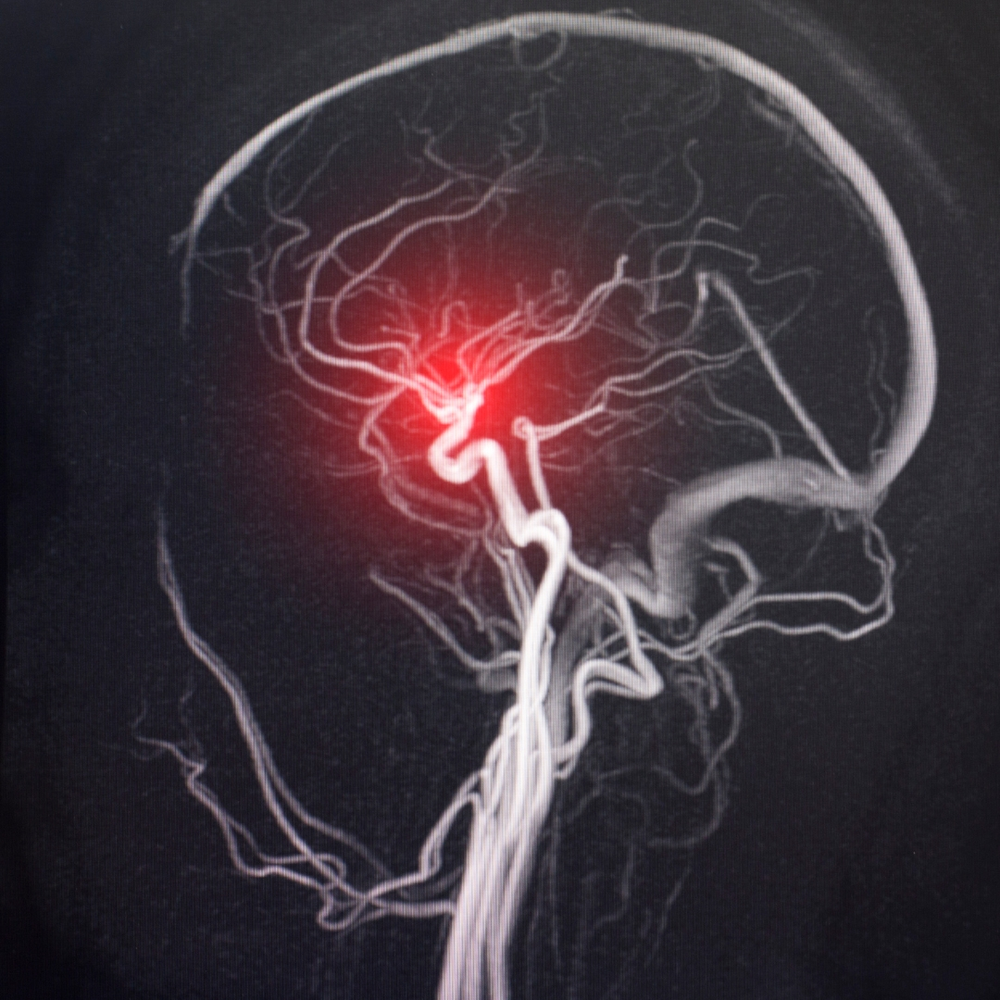

É uma disfunção em áreas do cérebro (loop córtico-estriado-talâmico)

O filtro que seleciona informações relevantes está “quebrado”, assim, pensamentos aleatórios começam a te perseguir.

3. Síndrome da Baixa Ativação: O Impacto das Regiões Cerebrais

Você já ouviu falar da síndrome da baixa ativação? Essa condição, envolve regiões cerebrais muito calmas e hiperativas de forma simultânea e tem sido associada ao TOC. nnA atividade cerebral irregular pode influenciar o desenvolvimento do transtorno.n